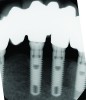

Fig 7 through Fig 14. Periapical radiographs of a 62-year-old woman who received a fixed porcelain-fused-to-metal reconstruction supported by abutments by internally connected dental implants. Fig 7 through Fig 10 are at initial prosthesis placement: mandibular site Nos. 30 and 29 (Fig 7); mandibular site Nos. 26, 25, and 23 (Fig 8); mandibular site Nos. 23 and 21 (Fig 9); mandibular site Nos. 21 through 19 (Fig 10). Fig 11 through Fig 14 are 11 years later (2013) and show excellent preservation of the vertical bone levels around the implants: mandibular site Nos. 30 and 29 (Fig 11); mandibular site Nos. 26 and 25 (Fig 12); mandibular site Nos. 25 and 23 (Fig 13); mandibular site Nos. 20 and 19 (Fig 14). It is interesting to note that in the mandibular right posterior quadrant there is a matched pair, ie, an external hex dental implant (No. 30) adjacent to an internally connected dental implant (No. 29). The bone levels around each of these designs are well-preserved at the 11-year follow-up.

During the first year after implantation, patients with completely restored edentulous ridges demonstrated a mean total bone loss ranging from 0.90 mm to 1.64 mm.58-60 After the first year, the mean annual rate of bone resorption ranged from 0 mm to 0.15 mm58-65 (Figure 1 through Figure 14).

Accordingly, if an increased rate of bone loss was selected to represent the pace of osseous resorption under dentures, a comparison between the rates of bone loss under dentures and around implants would indicate that implants preserve bone. Furthermore, the preponderance of data document that usually the amount of bone reduction per year around implants, in the absence of peri-implantitis, is so small that it has a negligible effect on the survival of implants, and it would take years to manifest noticeable bone loss and recession. For example, in areas under implant-supported prostheses (Figure 15), the ridge does not routinely manifest bone resorption and recession.66,67 However, there are patients who demonstrate different degrees of bone loss, and the reason for this is unknown.